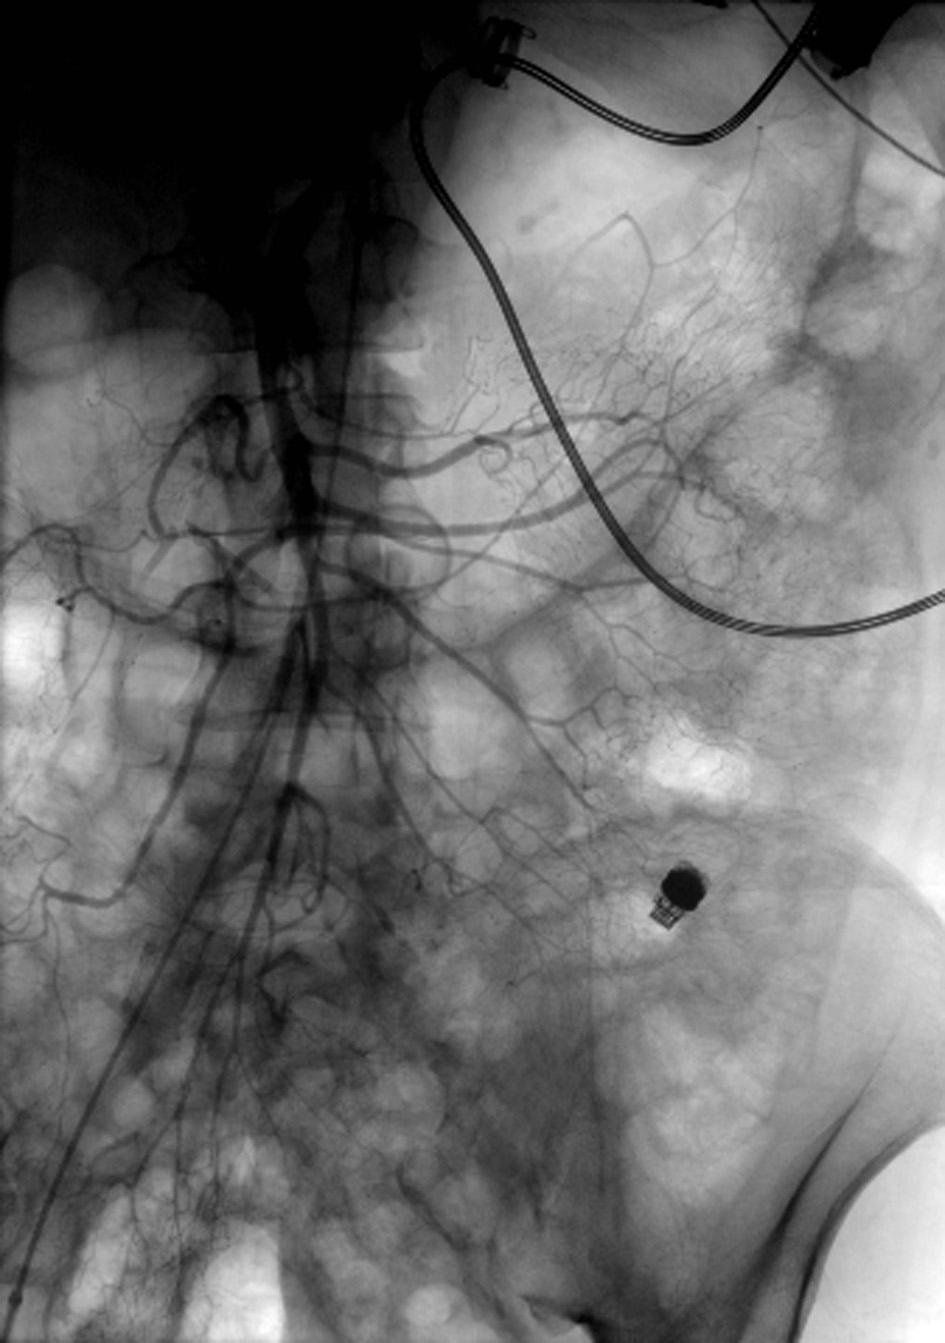

A 55-year-old male with dilated cardiomyopathy, atrial fibrillation, internal cardiac defibrillator, end-stage renal disease on hemodialysis, and iron deficiency anemia was transferred to our institution for LVAD placement. Esophagogastroduodenoscopy (EGD) and colonoscopy performed 4 months prior to LVAD placement to evaluate iron deficiency anemia were unremarkable. The patient remained hospitalized after HeartWare (Framingham, MA, USA) LVAD placement due to a complicated course including fungemia, ventricular arrhythmias, and aspiration pneumonia resulting in cardiac arrest and intubation from which he subsequently recovered. Three months after LVAD placement, the patient was transferred to the intensive care unit (ICU) for septic shock and required norepinephrine and dobutamine infusions for vasopressor and inotropic support. The following day, the patient developed maroon colored stools in the setting of aspirin and therapeutic anticoagulation with decrease in hemoglobin (Hgb) from 9 to 6 g/dL. He was transfused six units of red blood cells (RBCs). Urgent EGD and colonoscopy without bowel preparation demonstrated bilious fluid in the duodenum and blood throughout the terminal ileum and colon; however, the bleeding source could not be identified. Given suspicion for a small bowel source of bleeding, a PillcamSB (Given Imaging, Yoqneam, Israel) capsule study was performed. The patient continued to demonstrate signs of active GI bleeding and a tagged RBC scan was performed concurrently, revealing active blood loss from the small bowel. Mesenteric angiogram (Fig. 1) of the celiac and superior mesenteric arteries did not reveal extravasation of contrast. The capsule study demonstrated active bleeding in the proximal jejunum, although the bleeding source was obscured by blood (Fig. 2, Supplementary Video 1, www.gastrores.org). Push enteroscopy reached the proximal jejunum without signs of blood or a source of bleeding. The patient was subsequently intubated for worsening respiratory status and continued to require dobutamine and norepinephrine for hypotension. After discussion with cardiology, anesthesia, and cardiothoracic surgery, the decision was made to perform antegrade DBE given ongoing requirement for anticoagulation in setting of an LVAD. DBE was performed at the bedside in the cardiac ICU. The double balloon enteroscope (Fujinon, Tokyo, Japan) was advanced 250 cm past the ligament of Treitz without any signs of blood or potential bleeding source. The suspected bleeding source was a proximal jejunal Dieulafoy’s lesion given the absence of mucosal lesions or angiodysplasia visualized on DBE. The patient tolerated the procedure without complication and his episode of bleeding ceased.

![]() Click for large image | Figure 1. Angiogram of the superior mesenteric artery without extravasation of contrast. Notice the LVAD with driveline in the left upper quadrant and the PillcamSB in the left lower quadrant. |